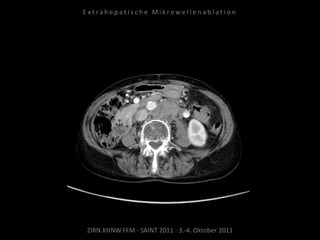

Bildgebung vor MWA:

CT vom 14.07.2010

Metastase lateral der linken Niere

nahe Colon descendens progredient.

Situation:

Metastasierung über längeren Zeitraum

lokal begrenzt,

1 Metastase progredient.

Organnahe Lage in unmittelbarer

Nachbarschaft zur linken Niere bzw. zum

Colon descendens.